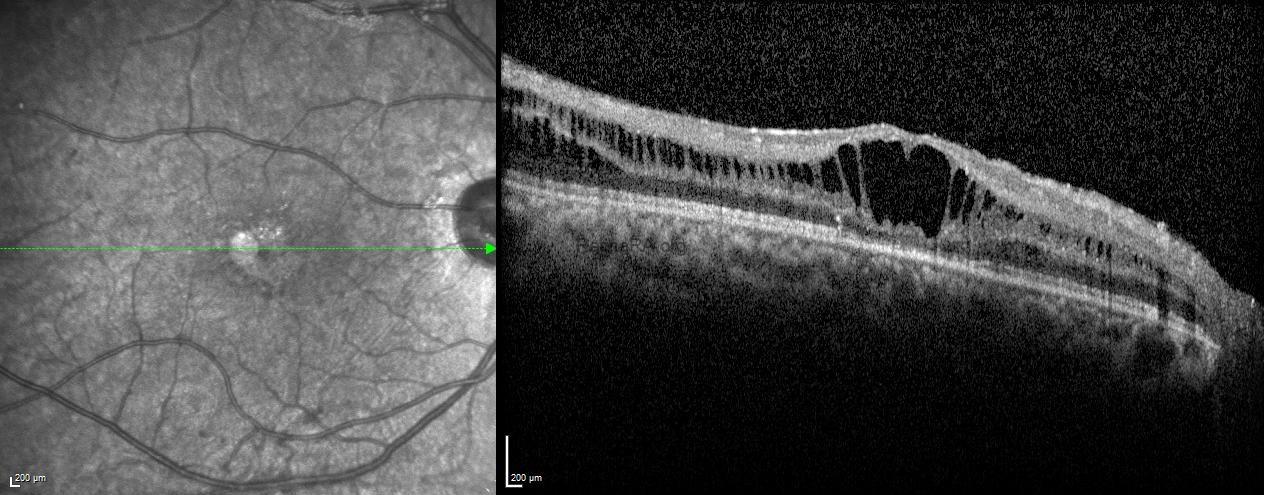

Optical coherence tomography (OCT) revealed diffuse cystoid spaces extending toward the optic nerve, causing splitting within the inner nuclear layer.

Fundus autofluorescence of the left eye showed alternating hyper- and hypoautofluorescent areas corresponding to the spoke-wheel pattern.